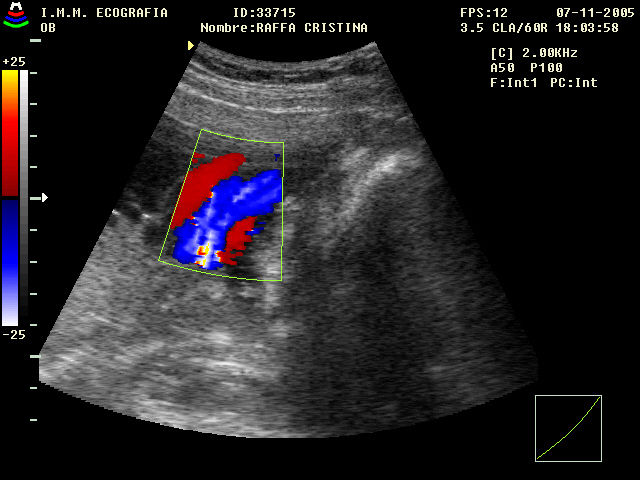

Ginecología . Obstetricia . Medicina Materno Fetal . Ultrasonido 4d HD Live

La consulta de evaluación de riesgos del embarazo tiene como piedra angular una historia clínica detallada, posteriormente la realización de estudios de rutina y finalmente, y de acuerdo con cada caso en particular, estudios especiales (laboratorio, ultrasonidos de nivel II). Al término de estos procedimientos, el médico especialista en ginecología y obstetricia está en la posición de poder establecer si un embarazo es de alto riesgo.